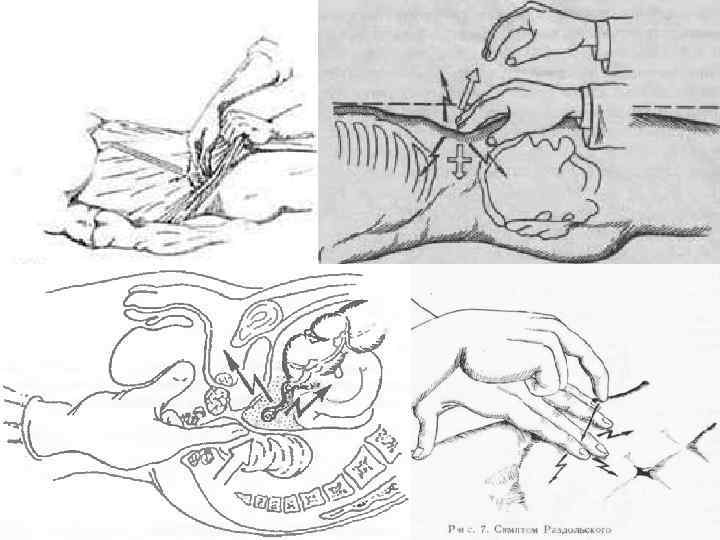

Клиническая картина Основные симптомы: Кохера Волковича – миграция боли из эпигастрия в правую подвздошную область. Раздольского – болезненность при перкуссии в правой подвздошной области. Воскресенского – скольжение правой рукой по натянутой рубашке от эпигастральной области к правой подвздошной с остановкой пальцев в проекции аппендикса. Ровзинга – прижатие в левой подвздошной области толстого кишечника вызывает усиление боли в правой подвздошной области. Образцова – усиление боли при поднятии выпрямленной в колене правой ноги. Ситковского – при перемещении больного на левой бок – усиление боли в правой подвздошной области. Бартомье Михельсона – болезненная пальпация в правой подвздошной области при положении на левом боку. Щеткина Блюмберга – сильная боль при пальпации в правой подвздошной области в момент резкого отнятия руки. Локальная/генерализованная ригидность мышц передней стенки брюшной полости. Симптом болезненности передней стенки прямой кишки – при «пальцевом» ректальном исследовании. Симптом нависания заднего свода влагалища – при влагалищном исследовании. Симптом «Токсических ножниц» учащенный пульс не соответствует температуре(при гангренозной форме).

Кохера-Волковича Воскресенского Щеткина-Блюмберга Ситковского Образцова Ровзинга Бартомье-Михельсона Раздольского